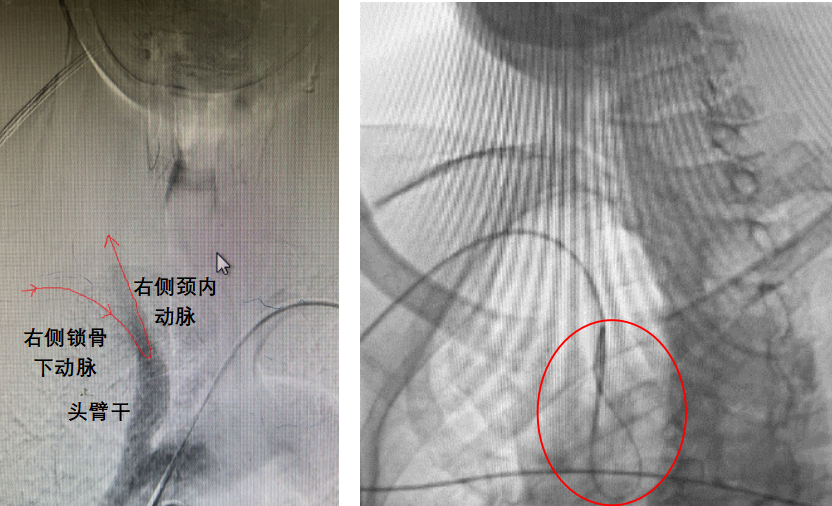

然而,又一个问题浮现在医师们眼前:脑血管造影提示老李右颈内动脉、锁骨下动脉形成锐利的夹角,也就是说,如果想要把导管送入右颈内动脉,就需要反折近乎180°!这为经桡入路带来极大挑战,不仅通路建立存在困难,还可能会出现支架输送不到位、输送过程中支架掉落、保护伞回收困难等多种技术上难题。经全面研究病历与影像资料,介入团队准备了联合方案与多套备选方案,向复杂路径的经桡颈动脉支架发起挑战。

导引导管入路示意图(左)与借助望远镜技术将导引导管“U型”送入右侧颈内动脉病变远端(右)

术中,在成功穿刺右侧桡动脉后,张小峰带领神经内科主治医师王也、医师沈懿,借助“望远镜”技术(同轴技术),先后将长导丝、造影管和导引导管送入至病变远端,以弥补普通导引导管无法通过迂曲血管的不足,随后采用球囊预扩张技术,对病变部位的血管直径及病变狭窄等情况进行探查。在撤出过程中,张小峰凭借经验及时调整系统张力,以球囊作为锚定点将导管精准定位,避免了术中容易出现的导管脱出问题。介入团队继续使用“特洛伊木马”技术,谨慎输送并于狭窄处精准释放支架。复查造影,右侧颈内动脉起始部的重度狭窄完全开通。不到1小时,手术顺利结束。